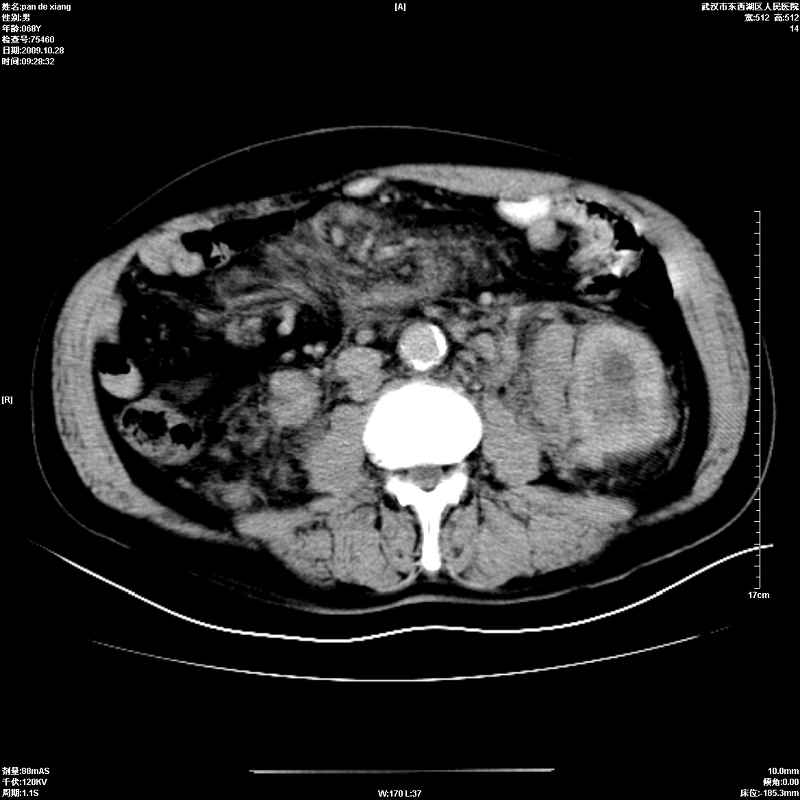

以下是引用杀毒软件在2009-10-28 20:41:00的发言:[br]结合临床考虑---白血病双肾改变或淋巴瘤。

以下是引用zxl51642在2009-10-29 9:59:00的发言:[br]结合临床“单克隆免疫球蛋白血症”,考虑双肾为继发损害并肾功能不全(尿中大量igg及少量iga、igm等大分子免疫球蛋白滤出所致继发损害),椎前软组织肿块为髓外造血。与浆细胞瘤有区别,平扫时有战友说的很清楚。